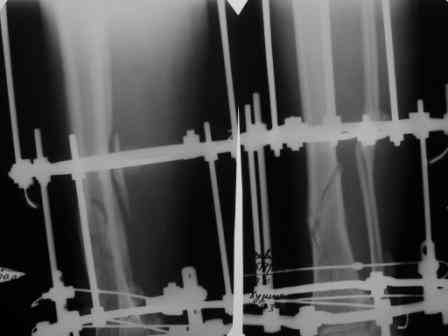

Сегодня мною была осмотрена больная, которой я выполнил накостный остеосинтез около четырех месяцев назад по поводу фрагментарного перелома бедра на уровне средней трети и межвертельной зоны.

Перелом синтезированный DHS сросся, а вот на уровне средней трети - нет. И, похоже, есть нехорошая тенденция к резорбции.

Больную беспокоит умеренный отек голени и стопы. Нагрузку на конечность не разрешаю, ибо недавно у молодого пациента при аналогичном переломе и остеосинтезе произошел перелом пластины на уровне нижней трети бедра...

Обращаясь к Александру Николаевичу, хочется узнать о целесообразности удаления металлоконструкции и интрамедуллярном штифтовании у них в институте у данной больной. Если есть резон, то нужно обговорить финансовую сторону вопроса ...

По поводу моей больной с фрагментарным переломом бедра ...

Больная 47 лет, поступила в отделение после автодорожной травмы от 08 июля сего года с DS: ЗЧМТ, СГМ. Закр. чрезвертельный перелом и перелом с/3 левого бедра со смещением. Ушиб и рваная рана левого коленного сустава. Соп.: Хр. железодефицитная анемия. (Гемоглобин при поступлении 71 г/л). 08 июля - ПХО ран колена.

11 июля остеосинтез бедра DHS + LC DCP.

Социальный статус ... пенсионер, не работает (вернее работает с детьми, частные предприниматели).

Я выкладывал на Форум этот случай, где высказывались опасения, что не исключается варусная дислокация межвертельного перелома на фиксаторе из-за малой длины Screw ... вроде пронесло ... перелом сросся. Но маленькая

победа в отдельной битве, все же не принесла победы в целом... Остается неопорная конечность, ограничение движений в коленном суставе 180 - 150 град., отечность голени и стопы, по-видимому, из-за сосудистой недостаточности, гипотрофии

мышц ноги ... При выписке из стационара Hb - 97 г/л (препараты железа, рибофлавины).

По настоящий момент наблюдается амбулаторно. Передвигается с опорой на костыли. Горит желанием встать "на крыло" ... Ждем Вашего решения. Может быть нужны дополнительные снимки?

Возьметесь ли за этот случай? Ну, и самое главное - стоимость лечения ...